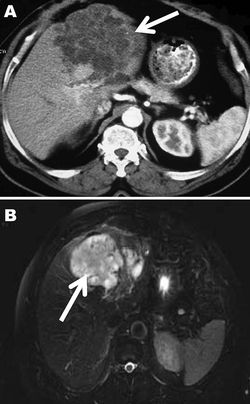

모든 유형의 포충증에 대한 공식적인 진단에는 영상 기술, 조직 병리학, 핵산 검출 및 혈청학을 포함하는 여러 방법이 사용된다.낭성 포충증(단방성 포충증) 진단의 경우, 주로 초음파 검사가 사용된다. 초음파 검사는 신체 장기의 낭종을 시각화할 수 있고[27], 저렴하며 비침습적이고 즉각적인 결과를 제공하기 때문이다.[28] 초음파 검사 외에도 자기 공명 영상(MRI)과 전산화 단층 촬영(CT) 스캔이 모두 사용될 수 있지만, 낭성 포충증을 진단할 때는 조직 내 액체 영역을 더 잘 시각화할 수 있기 때문에 CT 스캔보다 MRI를 선호하는 경우가 많다.[27][29] ''에키노코쿠스 과립osus''에 특이적인 항원을 사용하는 혈청 검사(간접 혈구 응집 반응, ELISA(효소 결합 면역 흡착 검사), 면역 블롯 또는 라텍스 응집 반응)는 영상 검사 결과를 확인하는 데 사용된다.

폐포성 포충증의 경우에도 초음파 검사가 가장 선호되는 영상 진단 기법이며, 전산화 단층 촬영(CT) 스캔으로 보완되는 경우가 많다. CT 스캔은 폐포성 포충증의 특징인 가장 많은 병변과 석회화를 감지할 수 있기 때문이다. 자기 공명 영상(MRI)도 초음파 검사와 함께 사용되지만, CT 스캔이 더 선호된다. 낭성 포충증과 마찬가지로, 영상 진단은 폐포성 포충증 진단의 주요 방법이며, 동일한 유형의 혈청 검사(''에키노코쿠스 다방포충'' 항원에 특이적)가 영상 검사 결과를 확인하는 데 사용된다. 혈청 검사는 ''E. multilocularis''에 더 특이적인 항원이 더 많이 사용 가능하므로 낭성 포충증보다 폐포성 포충증 진단에 더 유용하다.[23] 영상 진단 및 혈청 검사 외에도, 중합 효소 연쇄 반응(PCR)을 통한 ''E. multilocularis'' 감염 확인 또는 환자 조직 생검의 조직학적 검사는 폐포성 포충증을 진단하는 또 다른 방법이다.[27]